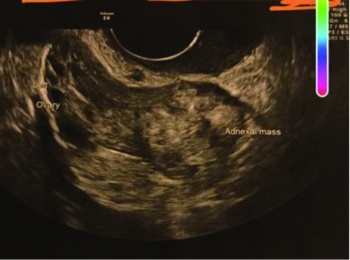

On presentation, she was vitally stable with blood pressure of 110/70. There was no tenderness, guarding and rigidity on abdominal examination. On per vaginum examination, no cervical motion tenderness was noted, with normal anteverted uterus. Urine pregnancy test was positive and beta hCG was 1,202 IU/L. Repeated levels of beta hCG were 1,355 IU/L and 1,898 IU/L. The patient initially declined any surgical intervention and opted for expectant management.

A day after the third level of beta hCG, the patient began complaining of severe lower abdominal pains and became hypotensive with blood pressure 80/45. A laparoscopy was performed due to severe pain and hypotension. Ectopic pregnancy was identified over the left ovary. Uterus, bilateral fallopian and right ovary were normal. There was pelvic haemoperitoneum and no signs of adhesions or Fitz-Hugh-Curtis syndrome (FHCS). Laparoscopic removal of left ovarian ectopic pregnancy was performed by diathermy scissors.